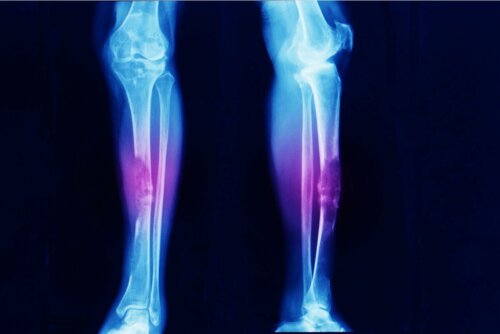

- Osteossarcoma: câncer ósseo.